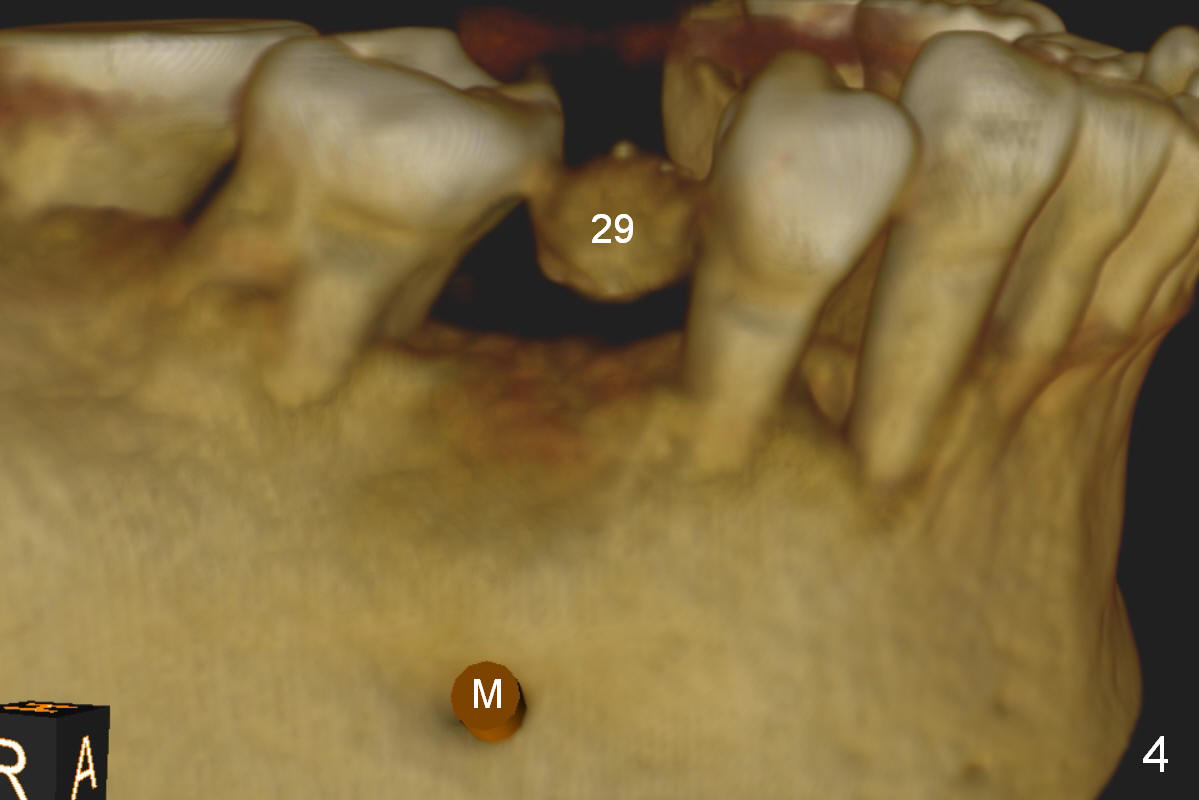

A 56-year-old man has long-termed partial edentulism (#2,5,14,15 (not shown),29, Fig.1). There is supraeruption of the opposing teeth (Fig.1 arrows). If an immediate provisional is provided, it should have plenty of clearance to avoid micromovement of the implant. Once the implants at #2,5, and 29 osteointegrate, they will be used as anchorage for intrusion (Fig.2,3 arrows, segmental orthodontics).

The first implant will be placed at #29 (Fig.4,5). The pointed ridge will be flattened to start osteotomy (Fig.6,7 (surgical handpiece)). The buccolingual dimension of the flattened ridge should be ~ 6 mm. The initial depth will be 12 mm. Take the 1st PA. A restorative high speed handpiece may be needed to remove the enamel of the mesial surface of #30 and the distal surface of #28 to increase space for implant placement.